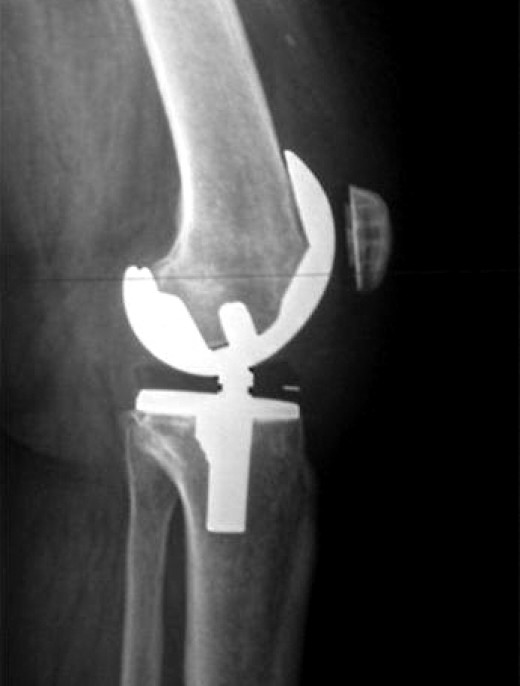

The Pros and Cons of Double Knee Replacement Knee replacement, Knee, Replacement